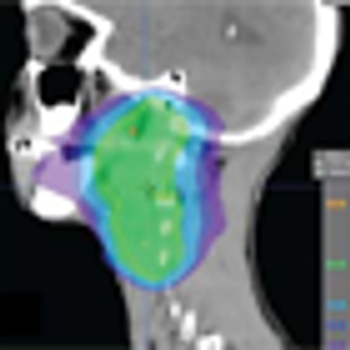

Researchers have identified several risk factors that may help predict which patients with oropharyngeal cancer may require a percutaneous endoscopic gastrostomy tube during chemoradiotherapy, according to a newly published review.

Black race did not adversely affect outcomes after receiving radiotherapy for head and neck squamous cell carcinoma compared with white race, according to the results of a study in which black patients made up the majority of enrolled participants.